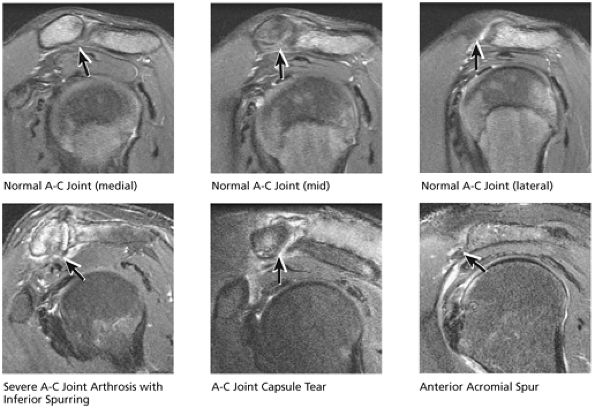

FIGURE 8.33 Acromioclavicular Joint.